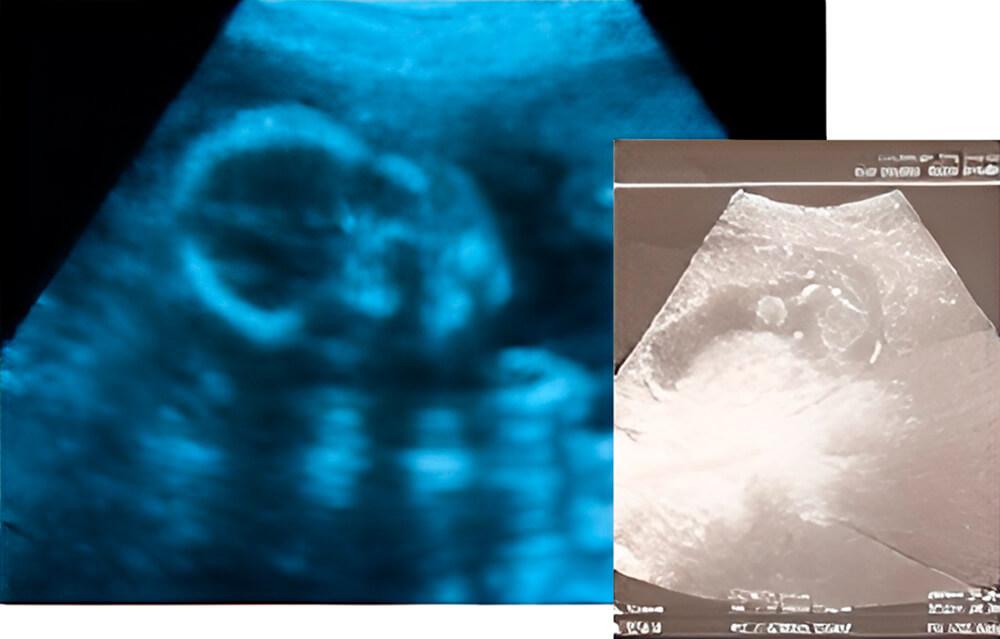

Lo que podemos ver en un ultrasonido

La foto muestra la cabeza del bebé. Las fontanelas se pueden ver entre los huesos del cráneo.

Después de que nazca el bebé, notarás dos puntos en la parte superior de su cabeza donde el cráneo es más blando. Se trata de las fontanelas (mollera), que son espacios del cráneo que aún no se han cerrado. Esto ayudará al bebé a pasar por el estrecho canal de alumbramiento [2, 4].